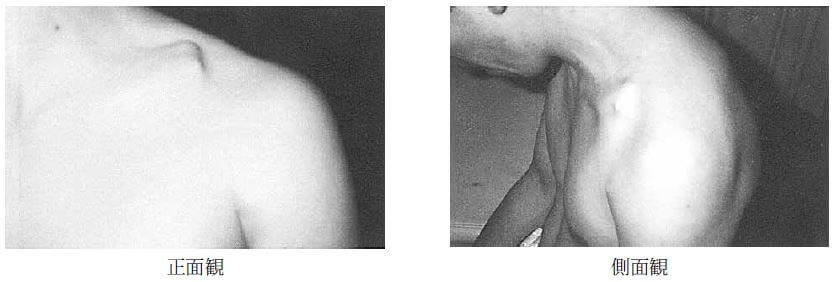

問題101.42歳の男性。スノーボードで滑走中、ジャンプの着地に失敗し左肩部を強打した。初診時の外観写真を下に示す。

この患者で適切でないのはどれか。

1.鎖骨の異常可動性が触知できる。

2.第3骨片が形成されている可能性が高い。

3.変形癒合を残しやすい。

4.患部を通過する絆創膏で圧迫した。

解答4

解説

・42歳の男性。

・スノーボードで滑走中、ジャンプの着地に失敗し左肩部を強打した。

・外観写真:鎖骨の連続性が絶たれている。

→本症例は鎖骨骨折が疑われる。鎖骨中1/3部骨折では、内側骨片は胸鎖乳突筋により上方へ引かれ、外側骨片は腕の重みで下方に転位する。

1.〇 鎖骨の異常可動性が触知できる。なぜなら、鎖骨が骨折すると骨連続性が断たれ、骨折部で異常な動きを触知できるため。

2.〇 第3骨片が形成されている可能性が高い。なぜなら、鎖骨には多くの筋・靱帯が付着しており、牽引力が不均等なため骨折部が粉砕しやすいため。特に、鎖骨中1/3骨折では、肋鎖靭帯や三角筋、僧帽筋などが異なる方向に牽引するため、中央に小骨片(第3骨片)が生じやすい。

3.〇 変形癒合を残しやすい。なぜなら、鎖骨骨折の転位を完全に整復固定することが難しいため。したがって、鎖骨骨折に対して、保存療法後は、「肩幅が狭くなった」「骨が出っ張っている」と訴える例は多い。

・変形癒合とは、位置がずれたまま癒合した状態であり慢性状態である。整復不良に起因し、骨癒合後に明らかになる。

4.× 患部を通過する絆創膏で圧迫「することはしない」。なぜなら、鎖骨骨折部を絆創膏や包帯で圧迫すると、骨片の転位や疼痛悪化、神経・血管の損傷を引き起こすおそれがあるため。 正しい固定法は「8の字帯」や「鎖骨バンド」であり、これは肩を後方に引いて骨折端を合わせるものである。